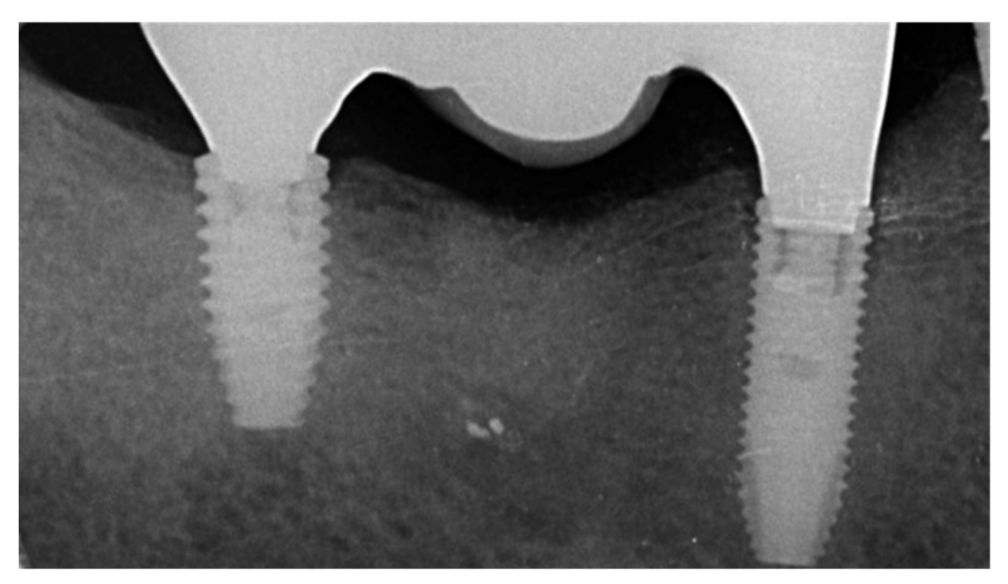

Implants fracture is an untreatable condition. There are several tools that may help clinician to remove the implant. However, fractured implant often presented damaged implant-abutment connection, hence, implant retrieval tools/kits (Figures 1–4) may not work. In cases implant is severely damaged and/or the residual osseointegration is very strong, such us in the mandible, the only possibility is to use a trephine burs (Figures 5–10).